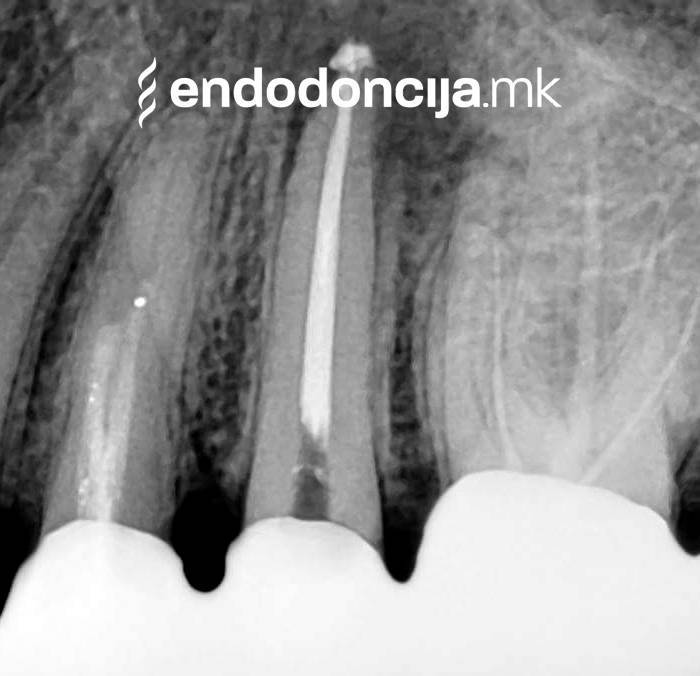

Εκτός από την ανίχνευση των ριζικών καναλιών, η ενδελεχής προετοιμασία και η απολύμανση του ριζικού σωλήνα είναι η προϋπόθεση για μια επιτυχημένη συνολική θεραπεία. Μέσω της χρήσης των νεότερων οργάνων και αντιβακτηριακών διαλυμάτων, όλα τα υπολείμματα ιστών και τα βακτήρια που υπάρχουν μπορούν να εξαλειφθούν.

Κατά τη διάρκεια της επεξεργασίας του ριζικού σωλήνα, τα λεπτά όργανα ενδέχεται να σπάσουν. Αυτό μπορεί να αποτελέσει εμπόδιο για την πλήρη προετοιμασία και τον καθαρισμό του ριζικού σωλήνα. Με μια μικροσκοπική επεξεργασία του ριζικού σωλήνα μπορεί να είναι δυνατή η απομάκρυνσή τους υπό ορισμένες συνθήκες, χωρίς να καταστρέφεται η ουσία των δοντιών.